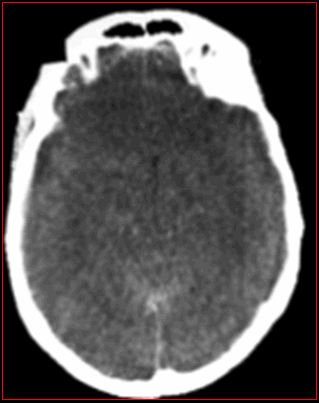

Phù não trên hình ảnh CT scaner

Có thể do tăng tính thấm mao mạch, do rối loạn chuyển hóa trong tế bào, rối loạn hoạt động kênh natri phụ thuộc ATP, do Gradien áp lực xuyên màng nội tủy

Phù não (xóa các rãnh não - bể não - não thất; mất ranh giới chất trắng - chất xám)